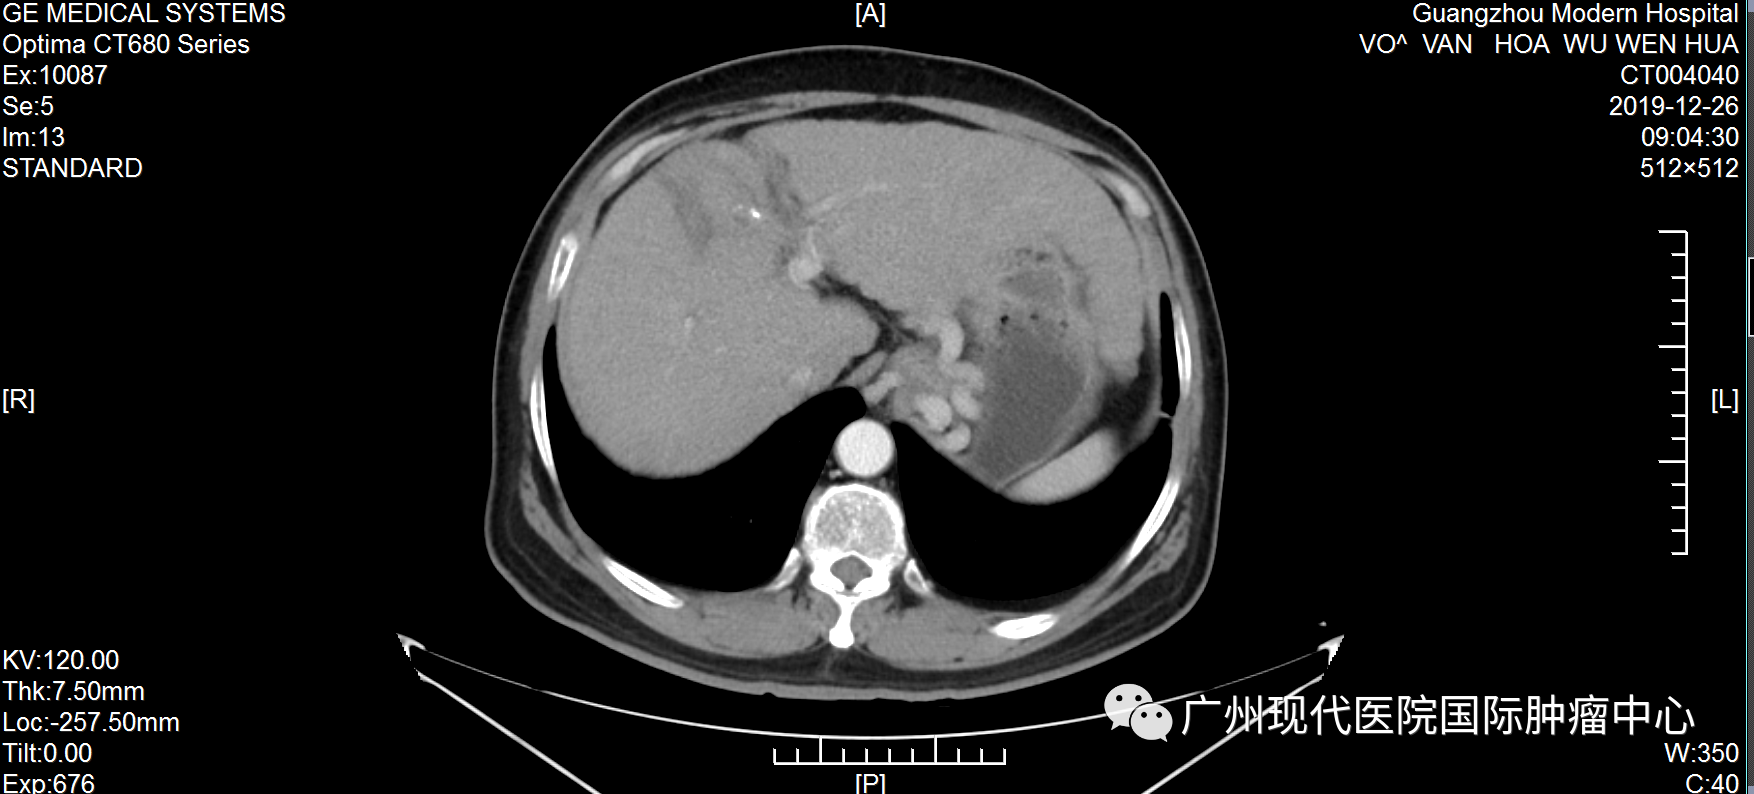

不愿做手术, 弟子推荐好医院 武文华自10岁起出家,年轻时,一直去各大佛寺学习佛教知识和游历,直至1999年时确诊丙肝,此后一直坚持吃药治疗。不曾想,时间的指针转到2019年,丙肝恶化为肝癌。 2019年6月,武文华因反复劳累出现低热,伴随右上腹胀痛、头痛等症状,且面部神经受影响,尤其是下颌与唇部麻痹且疼痛。随后,他到当地医院就诊,做腹部CT检查,初步诊断为肝细胞肝癌、肝硬化。当地医生建议做手术,武先生不愿意开膛破肚,也担心手术风险、术后感染等问题,于是拒绝越南医生的治疗方案。 武文华和妹妹及弟子合影 机缘巧合下,武文华的弟子了解到自己的一位亲友在一家口碑很好的癌症专科医院——圣丹福广州圣丹福肿瘤医院获得了很好的治疗,现在肿瘤已经完全消失了。弟子把这家医院推荐给武文华,告诉他不用开刀也能很好地治疗癌症,并给他介绍最新的微创技术。“不用开刀”这一技术优势深深地吸引了武文华,他很快找到胡志明办事处咨询,并在工作人员的帮助下来到广州。 微创综合治疗, 让他重获新生 2019年7月,武文华来到圣丹福广州圣丹福肿瘤医院。根据他的病情,医院MDT医疗团队研讨决定,给予他综合微创治疗方案。 第一次住院期间,武文华先后接受介入治疗、纳米刀等微创治疗。介入治疗可以切断癌细胞营养供给,抑制肿瘤生长,减少肿瘤转移,直至彻底杀死肿瘤;而纳米刀是一种全新的尖端肿瘤消融技术,通过电极探针释放高压脉冲击穿肿瘤细胞的细胞膜,形成多个纳米级不可逆的电穿孔,破坏细胞膜,从而破坏癌细胞组织,使细胞快速凋亡。他曾经的主治医生马主任表示,这个治疗方案,非常适合武文华这种不愿接受传统治疗、甚至对放化疗已经产生耐受性的癌症患者。 2019年武文华住院期间生活照 据了解,入院前,武文华体内的肿瘤大小为70*60mm。经介入栓塞治疗和纳米刀治疗后,肿瘤缩小到22*16mm。回忆治疗过程,武文华表示:“因为不需要开刀,每一次微创治疗都在半小时内结束。做介入治疗时,没有任何痛感,第二天就可以下床。纳米刀是在全麻的情况下做的,没什么感觉。” 治疗1个月后,肝部肿瘤明显缩小 治疗5个月后,肿瘤已基本消失 活动中,马主任回忆称:“他总共接受了5次介入治疗和纳米刀治疗,综合治疗完成后,肝部的肿瘤基本消失,他头痛发烧及面部神经影响等问题也得到了解决。”肿瘤消失后,为了巩固治疗效果,他遵守医嘱再次入院并接受了免疫治疗。 自2019年7月至今,武文华已经抗癌成功5年了,这对于他的家人而言是一种莫大的幸福。他的妹妹欣喜地说:“此前在越南的医院,医生下结论说他不做手术只能活3个月,如果做手术成功率只有30%。时间证明我们选择来广州治疗是对的,现在他每年仍然在越南定期检查,结果完全稳定,而健康的状态现在已经延长了5年,这是一个奇迹!” 医患情暖人心, 定下十年之约 这是武文华第三次回到医院。在采访中,他表示:“我完成治疗返回越南后,新冠疫情就爆发了,我像往常一样进行寺庙的日常管理工作,还积极参加抗疫的工作,我很幸运能够那么快地恢复健康,这要归功于医院的精心治疗和护理。” 住院期间,因为面部神经不适等症状,武文华被我院医护人员悉心照料照顾,他为之动容并为他们创作了一首诗:“别时合影它日忆,此处高风妙可夸。天使殷勤通昼夜,良医吐哺映莲花。”谈起写诗的初衷,他说:“我曾经在别的医院治疗过,后面依然选择这里,是因为这里的医生和护士都非常专业,对病人热情而周到。” 2019年,武文华出院时为我院赋诗及合影 活动中,武文华和主治医生马主任合影 他以亲身经历,对其他患者强调,肿瘤不是一种绝对导致死亡的疾病,而是一种慢性病。“现在我能够正常地饮食,工作,还能进行体育锻炼。如果你确诊了癌症,请不要灰心,不要悲伤,一定要遵守医嘱,相信自己可以恢复健康。” 抗癌明星的聚会中,马主任仔细聆听他的分享,不断绽放出感动与欣慰交织的笑容。她难掩心潮澎湃,还定下一场“十年之约”:“看到武大师目前拥有这么健康的状态,我感到我们医护人员所有的努力和付出都是值得的。希望十年后和大家再相聚!” 活动后,武文华还同其他抗癌明星们一起,体验了一场精彩纷呈的广州之旅。他们夜游珠江,体验现代都市的繁华;结伴同游宝墨园,观中华文化的博大精深。他们的癌后余生,正如脚下的路,徐徐绵延向前,充满阳光! 微创治疗技术简介 纳米刀:是一种全新的肿瘤消融技术,源于不可逆电穿孔技术,通过电极探针释放高压脉冲击穿肿瘤细胞的细胞膜,形成多个纳米级不可逆电穿孔,破坏细胞内外平衡,使细胞快速凋亡。治疗优势是时间短、 治疗区域的血管、神经等重要组织得以保留、安全可靠等。 1、具备创伤小、并发症少、安全、恢复快的优势。 2、可适应更多复杂的病情,包括胰腺、肝、肺、肾、前列腺以及其他实体肿瘤 介入治疗:在医学影像设备引导下穿刺,利用特制导丝等精密器械,将比静脉点滴药物浓度高2~8倍的抗肿瘤药物直接注入肿瘤内部,同时对肿瘤的供血动脉进行栓塞,实现肿瘤缩小甚至消失的目的。 1、具备创伤小、并发症少、安全、恢复快的优势。 2、适合采用传统放化疗效果不佳、不愿或不适合做手术等情况的患者。